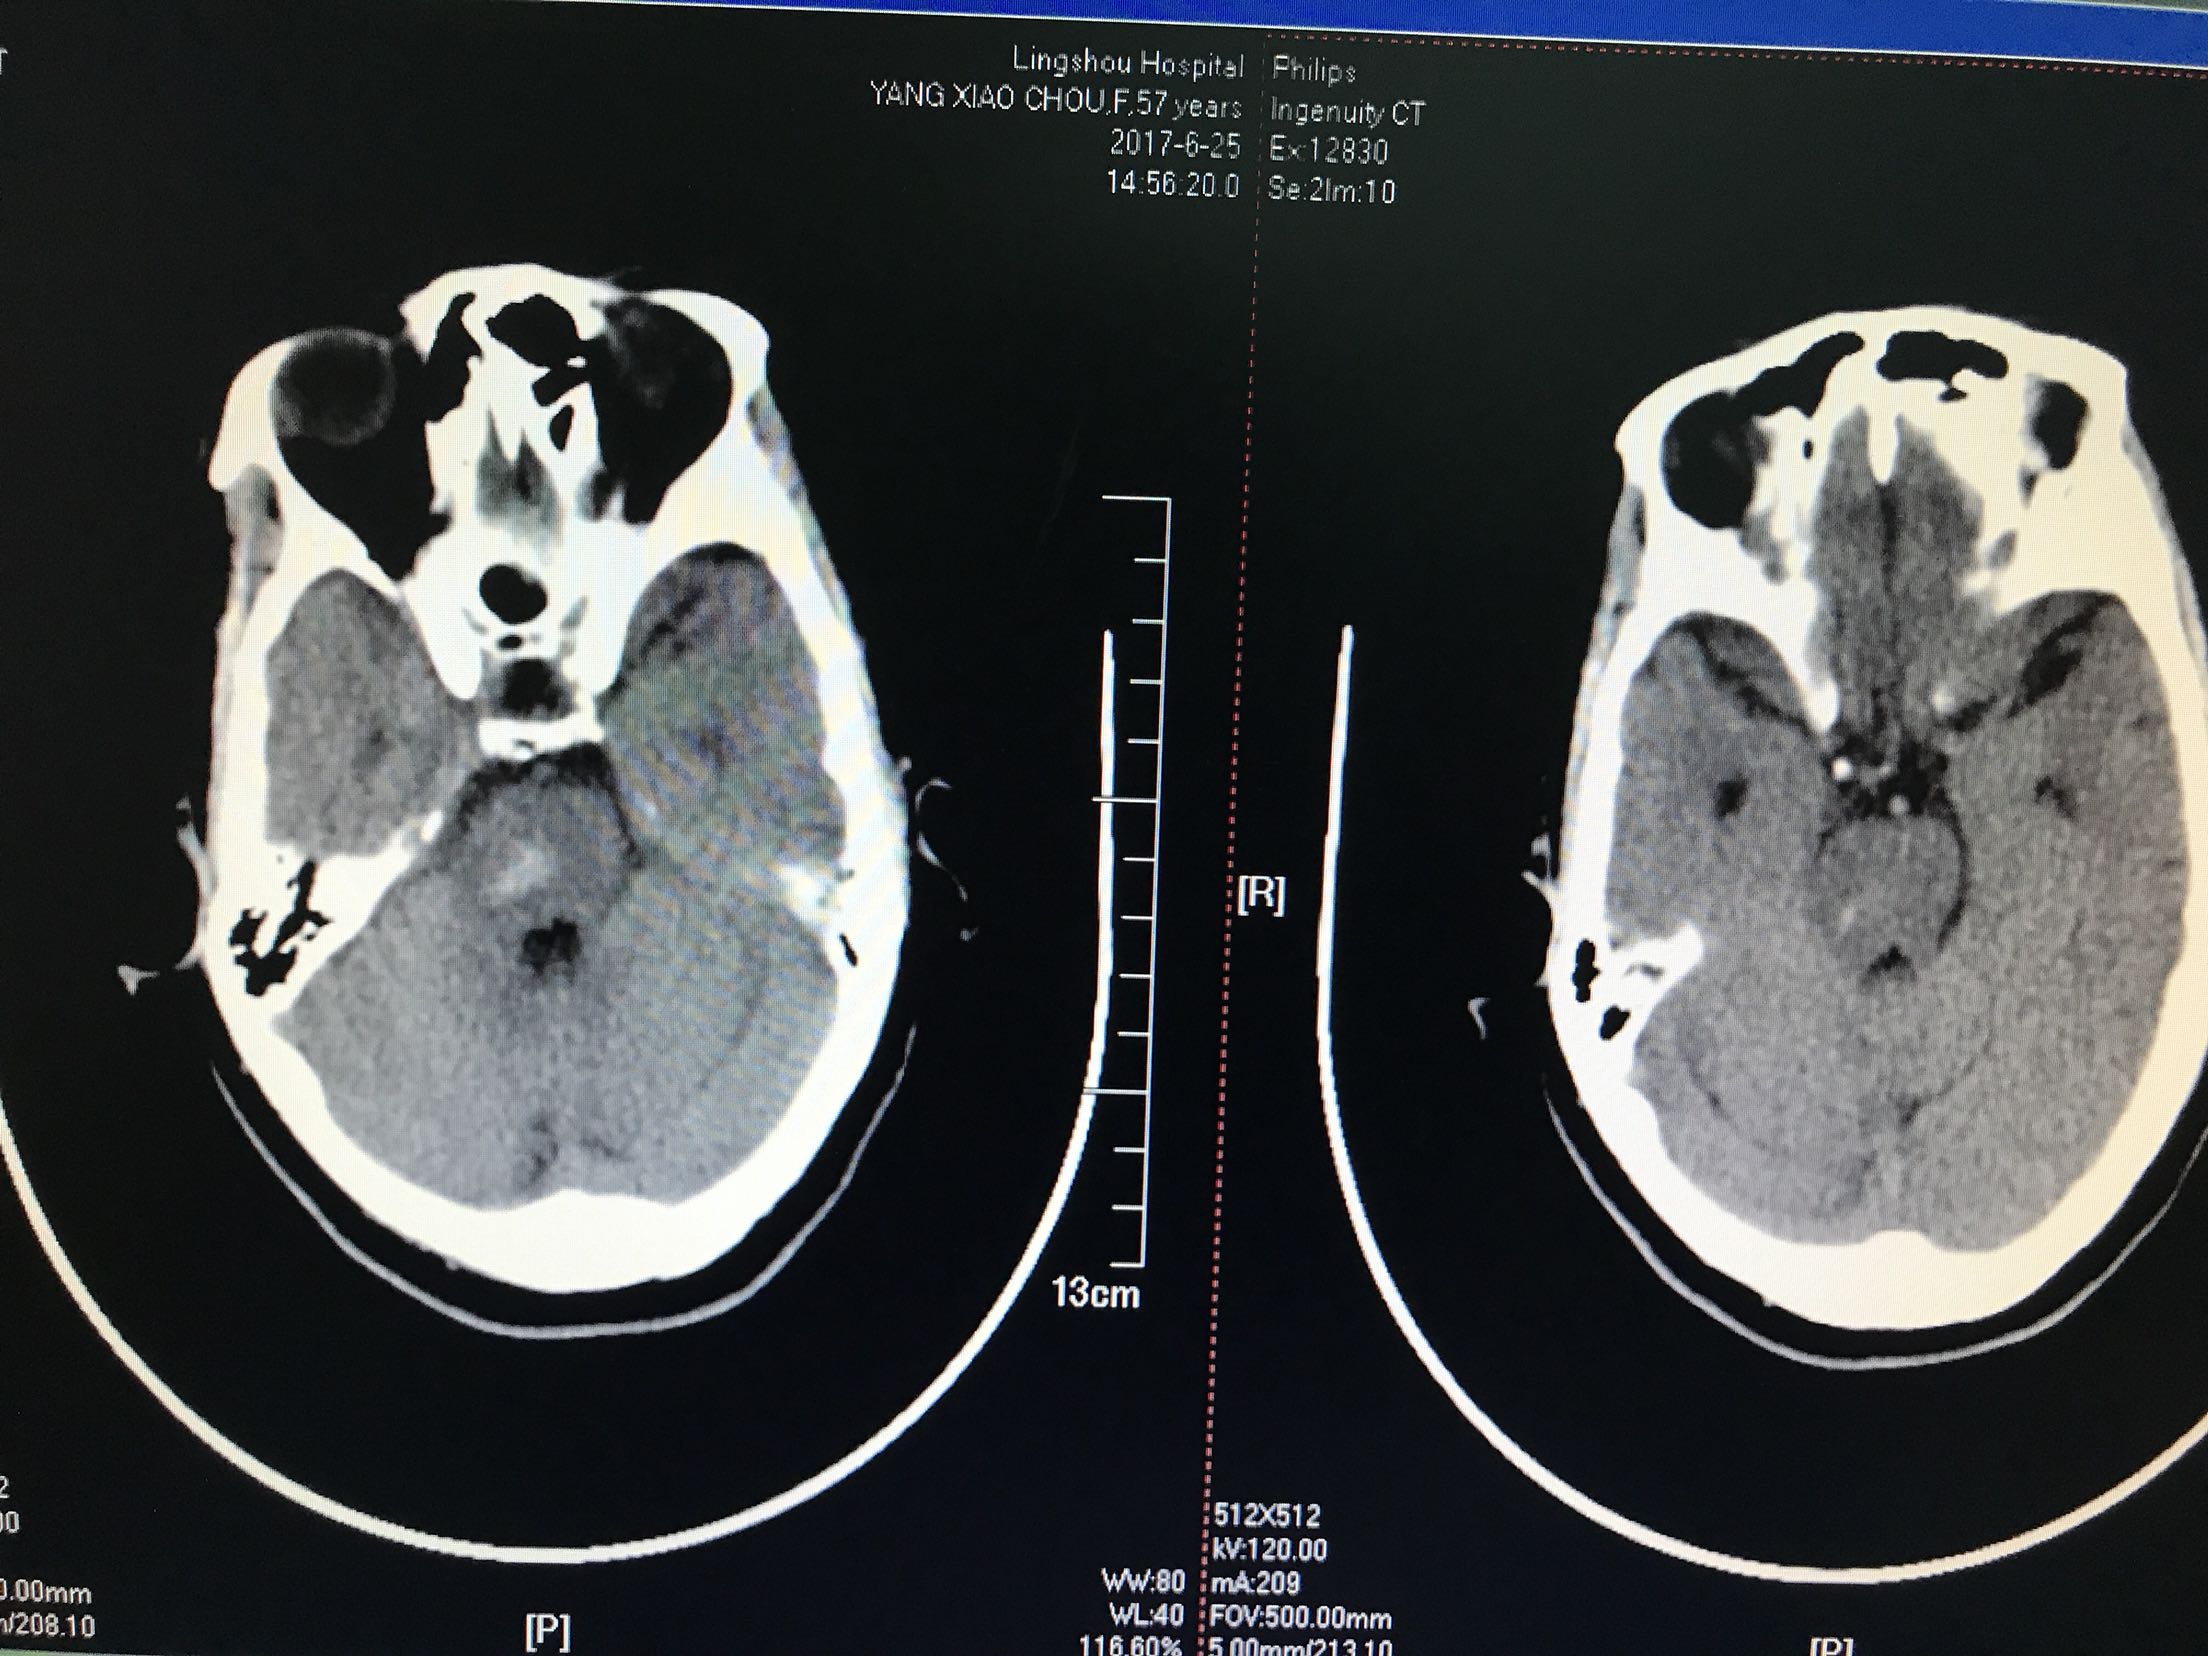

患者主因言语不利,右侧肢体无力2小时入院,患者中年男性57岁,既往"高血压,脑梗死"病史,未留明显后遗症,未监测血压,患者入院前2小时无明显诱因出现言语不利,右侧肢体无力,听理解无障碍,上肢不能抬举,下肢不能负重,伴左侧头痛,无头晕,恶心,呕吐,无饮水呛咳,急诊急查头CT:脑干出血,心电图示:房颤,为进一步治疗收住院

体温36.9℃ 脉搏50次/分 血压159/90mmhg,神清,运动性失语,伸舌右偏,双肺呼吸音清,未闻及干湿性啰音,心音有力各瓣膜听诊区未闻及杂音,腹软肝脾未触及,肠鸣音正常,双下肢无水肿,左侧上下肢肌力肌张力正常,右侧上下肢肌力0级,肌张力高,双侧巴氏征阳性

1.脑干出血2.房颤,药物给于止血,脱水降颅压等治疗,密切观察意识变化